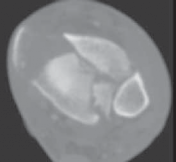

22.

Cole et al3 mapped 38 consecutive AO/OTA 43-C3 (complex articular) plafond fractures with CT scans and found that all plafond fractures in this category exited the tibiofibular joint laterally and at two separate locations medially to create a coronally oriented Y pattern with three major fragments ( FIG 2A). There were also varying amounts of articular comminution anterolaterally or anteromedially (FIG 2B).

--- A B ### FIG 2 • A,B. CT images from 43-C3 plafond injuries demonstrating typical fracture patterns with anterolateral, medial malleolus, and posteromedial fragments. Variable amounts of central or anterocentral articular impaction and comminution are commonly seen.

1. Isolated osteochondral fragments of variable size are often encountered (typically central to anterolateral in location; Fig 2B) and constitute the remaining portion of the articular surface.